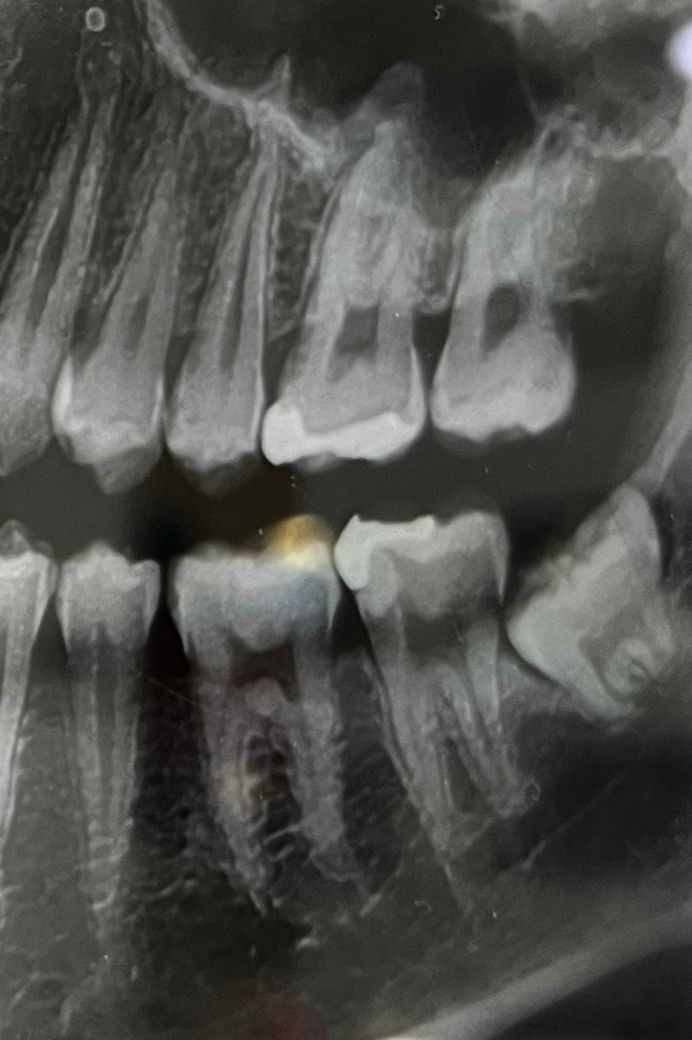

이 사진에서 충치가 확인가능한가요?

이 사진에서 충치가 있나요? 있다면 어디에 있는지 좀 알러주시면 감사하겠습니다. 제가 가는 치과에 의사는 없다는데 계속 아파서요.

현재 통증이 크게 느껴진다면 사랑니과 사랑니 앞의 치아 사이가 가장 의심되고 사랑니를 빼시는 게 좋아보입니다.

충치는 없는 것으로 보입니다. 사랑니가 묻혀 있어 이 사랑니 때문에 아픈 증상이 나타날 가능성이 높습니다. 일단 먼저 사랑니 뽑는 것을 추천합니다.

사진상으로 의심되는 부분은 아래쪽 사랑니 포함 뒤에서 4번째 치아 뒤쪽으로 충치가 많이 진행된것처럼 보입니다. 작은 사진을 한번 찍어보시는게 좋을것같습니다 .

아래 두번째 큰 어금니 뒷면이 충치가 의심됩니다. 옆에서 매복되어 있는 사랑니가 영향을 주고 있을 확률이 큽니다. 다른 치과에서도 진단 받아보세요.